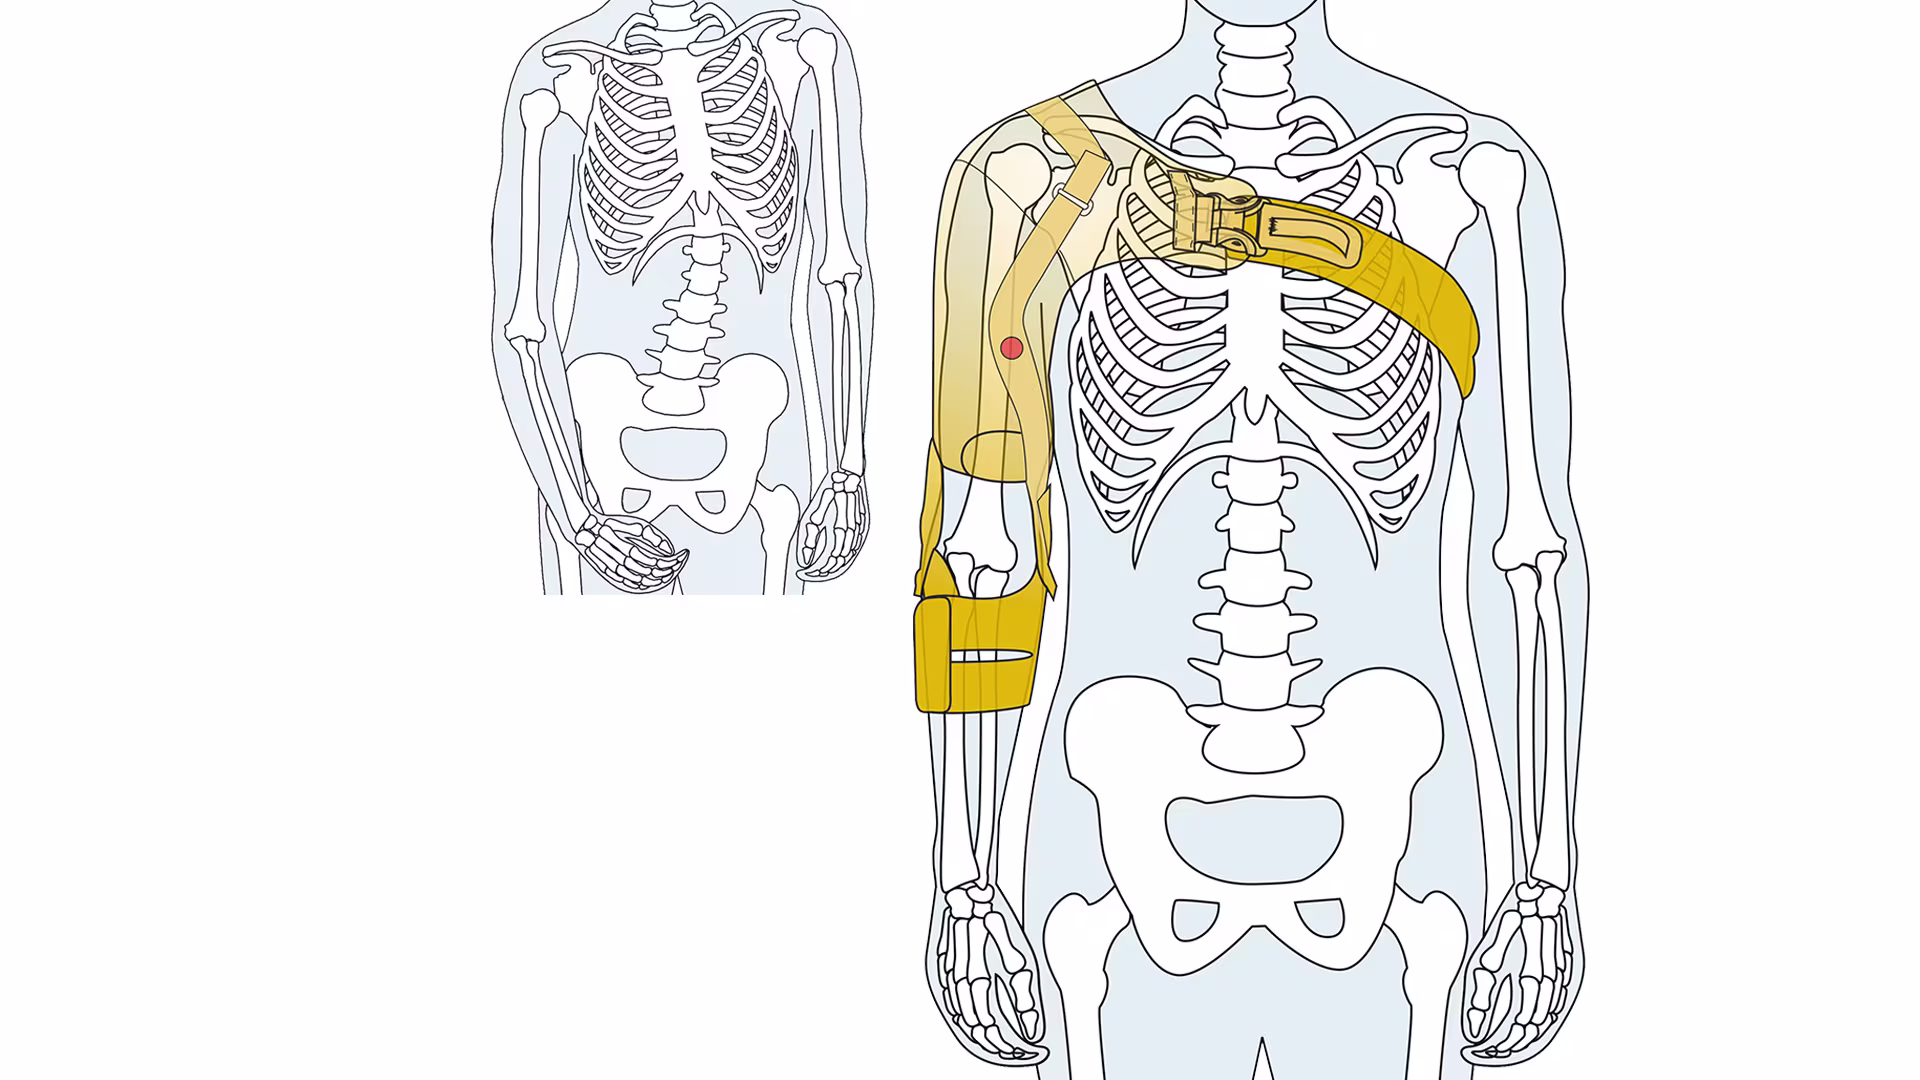

装着肢位の比較

前腕カフを連結し、引き上げることで上腕骨頭を関節窩へ引き寄せ、肩関節構成体への負担を軽減します。また、装着肢を肩関節外旋位、肘関節軽度屈曲位、前腕回外位に保持する構造になっており、自然肢位の保持(不良肢位・動作の改善)、歩行訓練時の体幹の安定効果が期待されています。